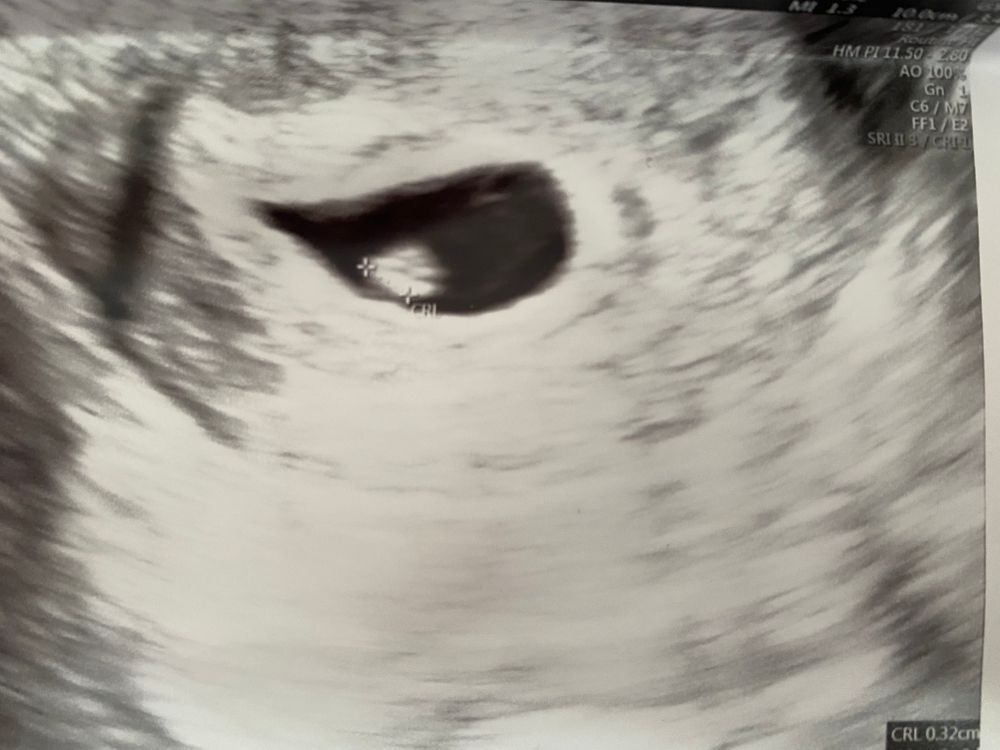

Узи в 6+4

Девочки, узи в 6недель+4 (4 и 4 от зачатия)

плодное яйцо -14мм

желточный мешок-3,2мм

КТР-3мм

сердцебиение 113 ударов в мин

узист говорит КТР маленький и сердце скорее всего вот вот забилось , как думаете все ли хорошо? КТР очень маленький? Волнует именно маленький эмбрион

следующее узи 23 мая, узист сказал что тогда точно видно будет🙏

Ещё,узист говорит что эмбрион не отделился от желточного мешка, такое бывает? что это значит?